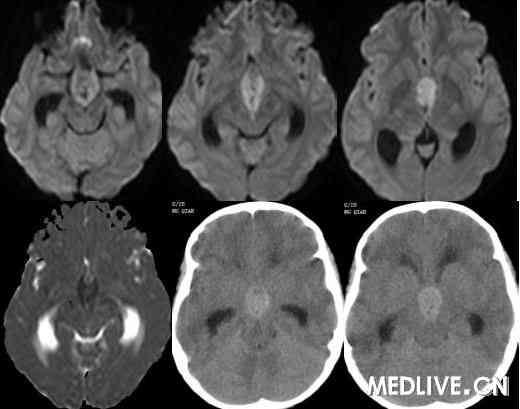

解答详情: 生殖细胞瘤由原始的生殖细胞衍生而来,好发于松果体区,其次为鞍上池。肿瘤多发生于男性青少年,位于鞍上生殖细胞瘤则以女性多见。生殖细胞瘤对放射线非常敏感。该瘤通常无包膜、无钙化、出血、坏死或囊性变,属低度恶性肿瘤,多呈浸润性生长,常有不同程度和形式的转移,易向蛛网膜下腔及脑室系统种植、播散。组织学上,肿瘤主要含有两种细胞成分:上皮样细胞和淋巴样细胞。 1、CT表现:  ①肿瘤最常见于松果体区,位于鞍上区肿块常累及漏斗;  ②CT平扫多呈等密度或稍高密度肿块,无出血、坏死及囊性变,可分叶,但境界清楚;瘤体本身钙化少见,典型松果体区生殖细胞瘤常见肿瘤包埋松果体钙化灶。  ③增强扫描呈中等至明显的均匀强化。  ④室管膜下转移可表现为沿脑室壁线状或条片状强化,沿脑脊液向蛛网膜下腔播散表现为脑表面、脑池的线状或结节状强化。   2、MR表现:  ①最常见于松果体区,也常见于鞍上,可同时或单独存在。②T1加权为略低信号或等信号,T2加权常呈等信号或高信号。③增强后;呈明显均匀一致强化,并能发现沿脑脊液或室管膜转移的病灶。鉴别诊断  1、颅咽管瘤:多为囊性或囊实性肿块,钙化多见。纯实性者可呈稍高密度,并可强化,与生殖细胞瘤不易鉴别、  2、星形细胞瘤:一般肿瘤较大,密度偏低,后期可出血,肿瘤通常位于下丘脑,并沿视交叉或视束延伸,可在眼眶内形成肿块。  3、垂体瘤:发生于鞍内,但可向鞍上生长,小儿罕见,肿瘤易出血、坏死,鞍底骨质变薄、下陷,海绵窦常受累。 生殖细胞瘤。4、脑膜瘤:好发于成人,儿童罕见,肿瘤部位偏前,伴骨质增生、硬化及蝶窦过度气化。